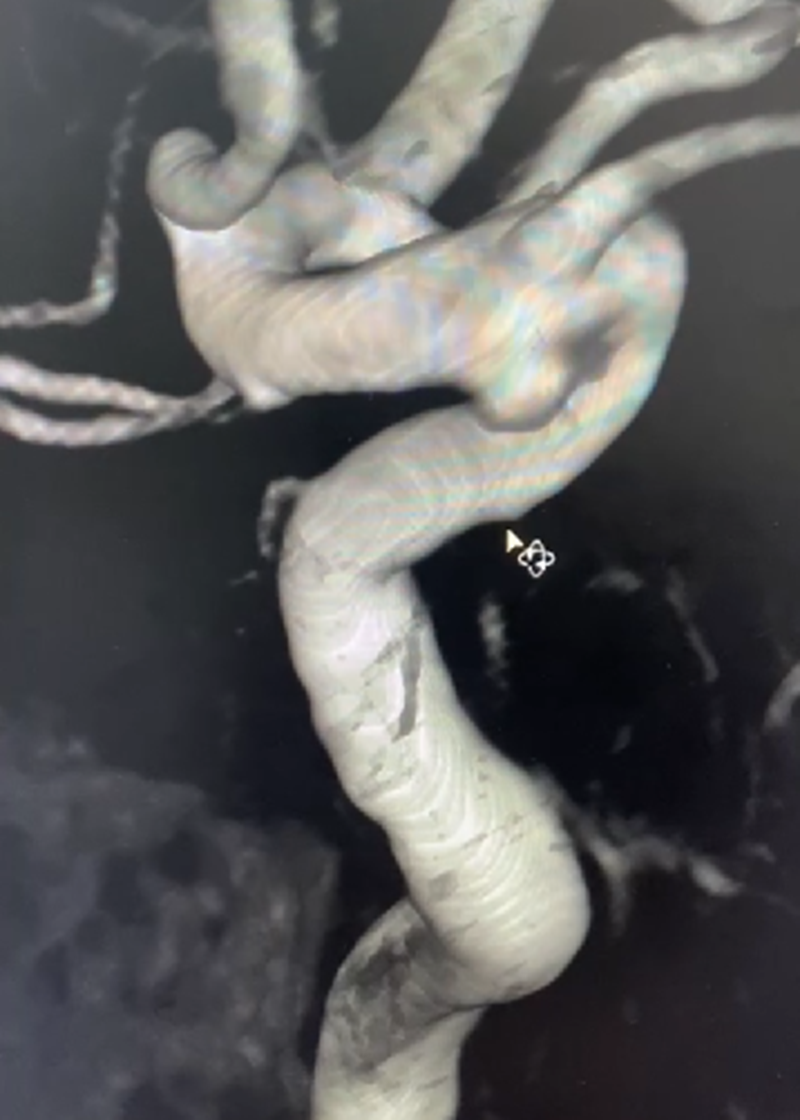

密网支架覆盖长度

▲术前3D测量

经检查,张某左侧颈内动脉C6段可见异常隆起,大小约为:2.6mm×2.1mm×2.3mm,考虑为动脉瘤,神经外科医疗团队经过多学科会诊和论证,决定为其实施目前国内外先进的血流导向装置进行介入治疗。